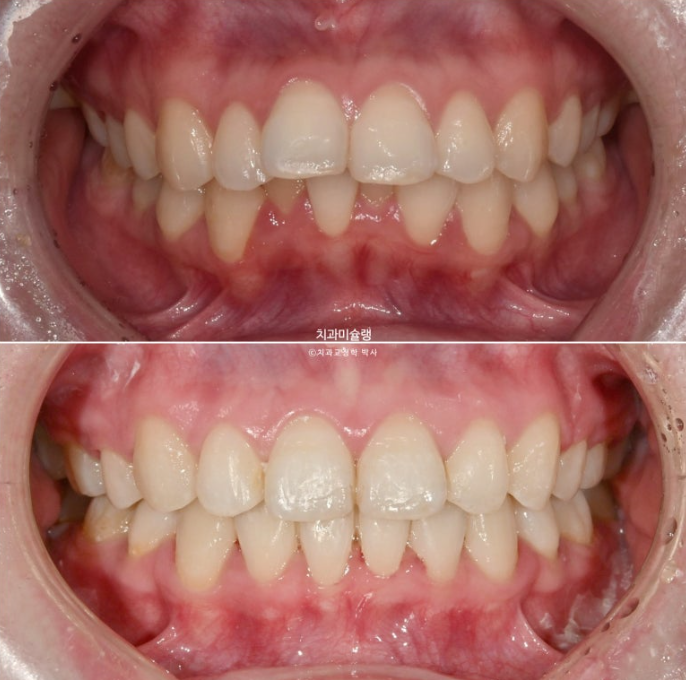

이제 전후 비교 보겠습니다.

어긋나 있던 중심선은 정확히 맞으며 깊게 물리는 과개교합이 해소되어 이제 아래 앞니가 정상적으로 보입니다.

뿐만 아니라 치아 높낮이 불규칙으로 인해 들쑥날쑥 했던 아래 앞니가 배열되면서 잇몸라인도 어느정도 정리가 되었습니다.

심하게 뻗쳐있던 앞니가 정상각도를 찾았습니다.

이제 비로소 입이 편하게 다물립니다.

입매는 과하지 않게 적정량 예쁘게 들어갔습니다.

돌출입이 해소가 되면 비순삭이 줄면서 코도 높아보입니다.

앞니가 뒤로 6mm 이상 들어갔고 통상 발치교정보다 더 많은 양이 들어갔지만, 교정 후 옥니 등 부작용은 보이지 않습니다.

치아의 변화만큼 입매 변화도 드라마틱 합니다.